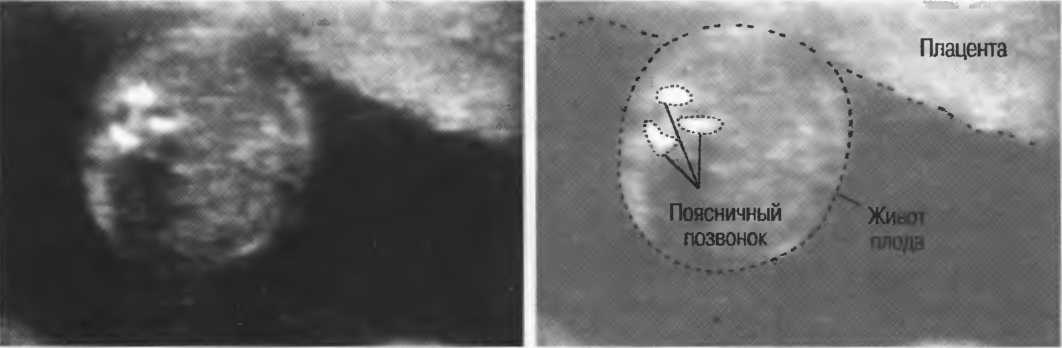

Рис.5. Два поперечных среза плода, демонстрирующих тень от позвоночника плода. Аналогичная тень от ребер может частично закрывать почки или печень. Изменяя угол наклона датчика, можно изменить положение тени таким образом, чтобы подлежащие ткани были видны отчетливо.